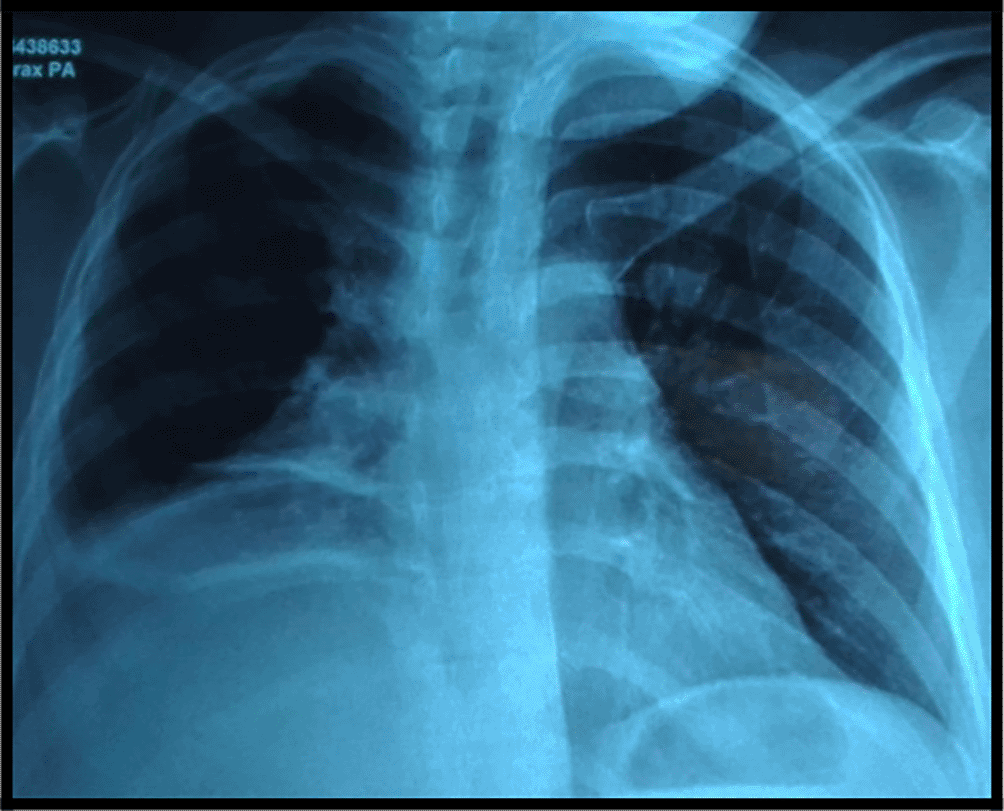

The chest x-ray showed a retractile opacity in the right chest with a hilar enlargement (Figure 1).

Atelectasis is the most frequent radiological finding, occurring in (2/3) of patients. Besides, the chest CT scan may reveal a solitary hilar mass or an obstructive emphysema. Mediastinal or hilar lymphadenopathy are often present.4